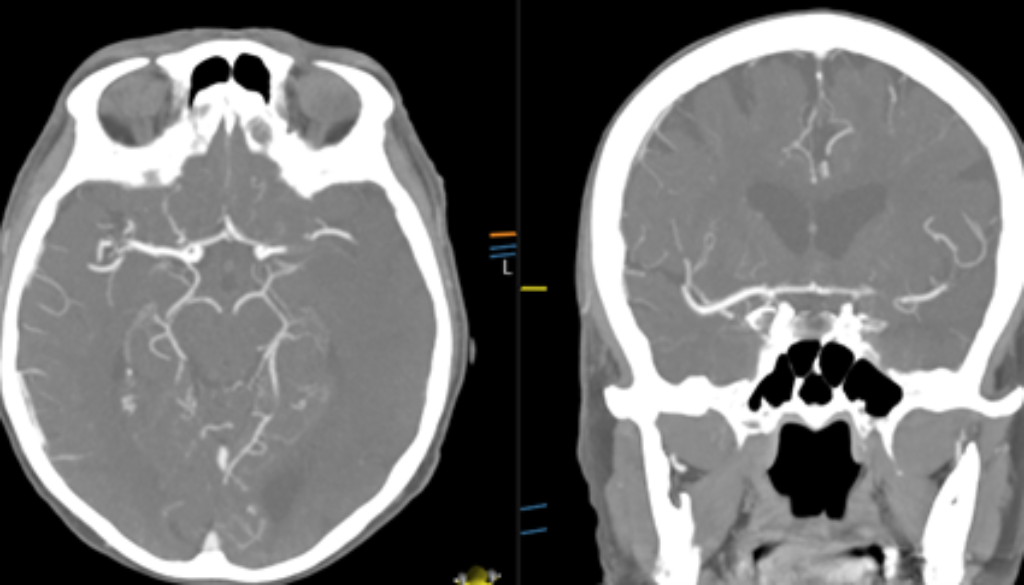

Occlusion (blood clot) on CT Angiogram